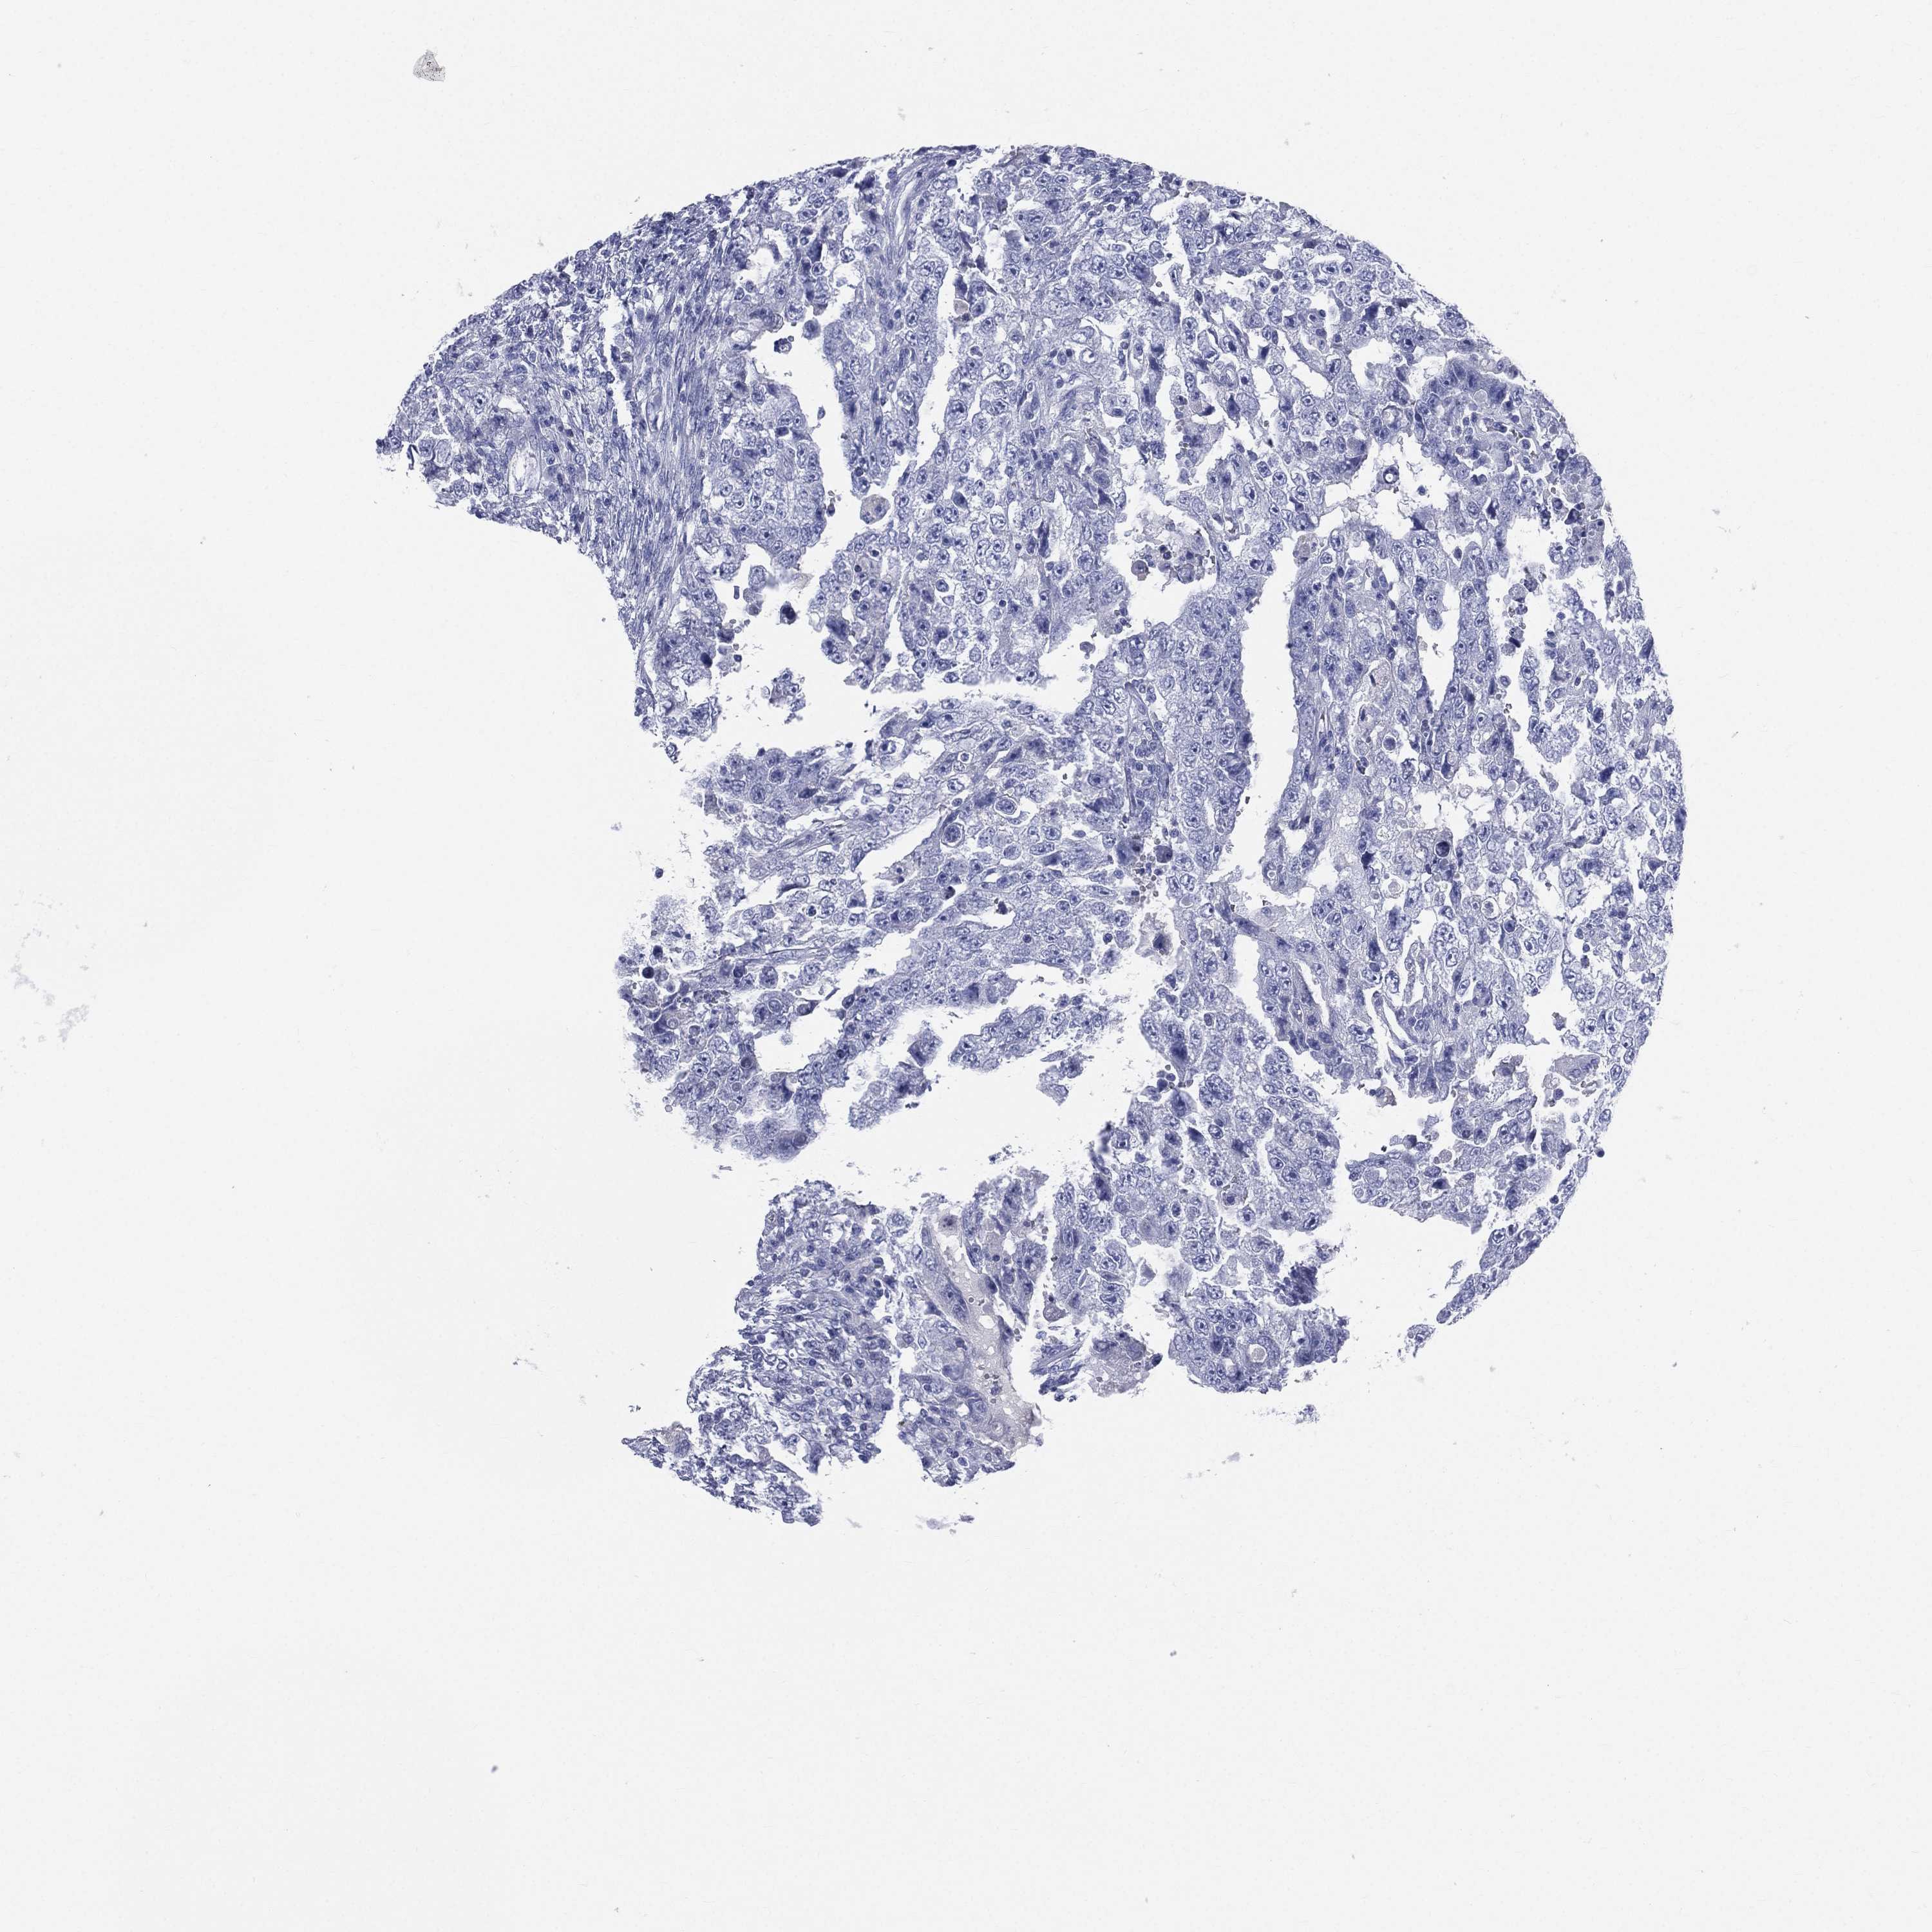

TESTIS CANCER - Protein expressioni

A mouse-over function shows sample information and annotation data. Click on an image to view it in a full screen mode. Samples can be filtered based on level of antibody staining by selecting one or several of the following categories: high, medium, low and not detected. The assay and annotation is described here.

Note that samples used for immunohistochemistry by the Human Protein Atlas do not correspond to samples in the TCGA dataset.

Antibody stainingi

Antibody staining in the annotated cell types in the current human tissue is reported as not detected, low, medium, or high, based on conventional immunohistochemistry profiling in selected tissues. This score is based on the combination of the staining intensity and fraction of stained cells.

Each image is clickable and will lead to virtual microscopy that enables deeper exploration of all samples and also displays staining intensity scores, fraction scores and subcellular localization as well as patient and tissue information for each sample.

Antibody HPA047750

Seminoma, NOS

Carcinoma, Embryonal, NOS